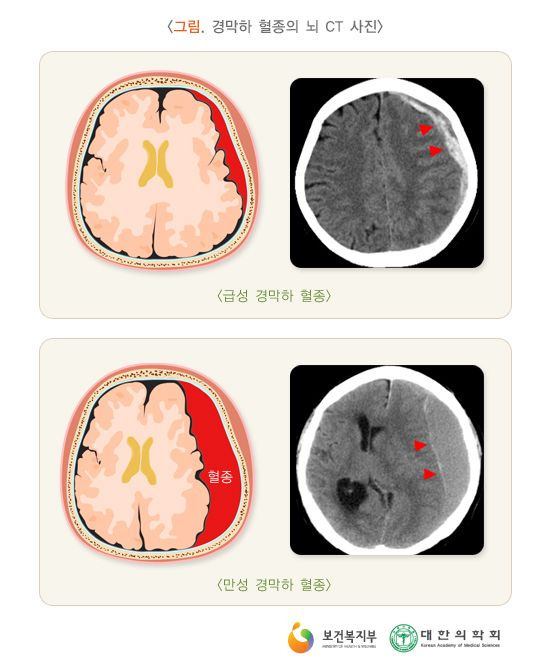

2. “뇌혈관질환”의 진단확정은 「의료법」 제3조(의료기관) 제2항(【부록】 참조)에서 규정한 국내의 병원, 의원 또는 국외의 의료관련법에서 정한 의료기관의 의사 면허를 가진 자(치과의사 제외)에 의하여 내려져야 하며, 이 진단은 병력·신경학적 검진과 함께 뇌전산화단층촬영(Brain CT Scan), 자기공명영상 (MRI), 뇌혈관조영술, 양전자방출단층술(PET), 단일광자방출 전산화 단층술(SPECT), 뇌척수액검사 등 을 기초로 하여야 합니다. 그러나 피보험자가 이 특별약관의 보험기간 중에 사망하여 상기 검사방법을 진단의 기초로 할 수 없는 경우 다음 중 어느 하나에 해당하는 때에는 진단확정이 있는 것으로 볼 수 있습니다.